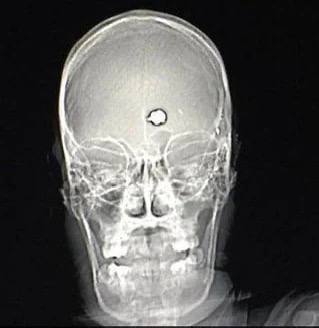

В соцсетях вспоминают реальный случай из 1980-х: американец с тяжёлым обсессивно-компульсивным расстройством (ОКР) выстрелил себе в голову из пистолета калибра .22.

Пуля вошла в левую лобную долю, отвечающую за навязчивые мысли. ОКР исчезло, а интеллект остался, и через несколько лет мужчина даже стал отличником в колледже.